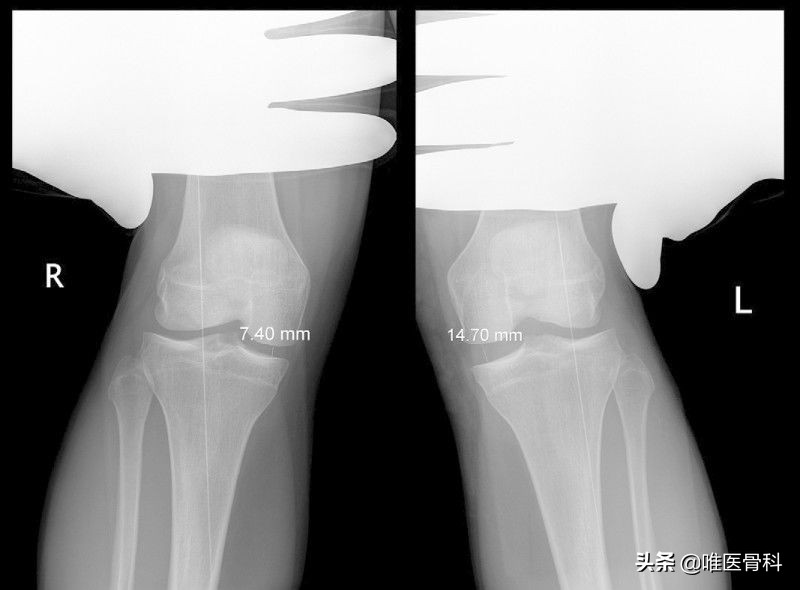

2)应力位X线片:即在外力下使膝内翻和膝外翻,需于局部麻醉后进行。在X线片上比较膝关节内、外侧关节间隙张开情况。

一般认为两侧间隙相差4mm以内为侧副韧带轻度扭伤;4-12mm为侧副韧带部分断裂;两侧间隙相差在12mm以上为完全性断裂。